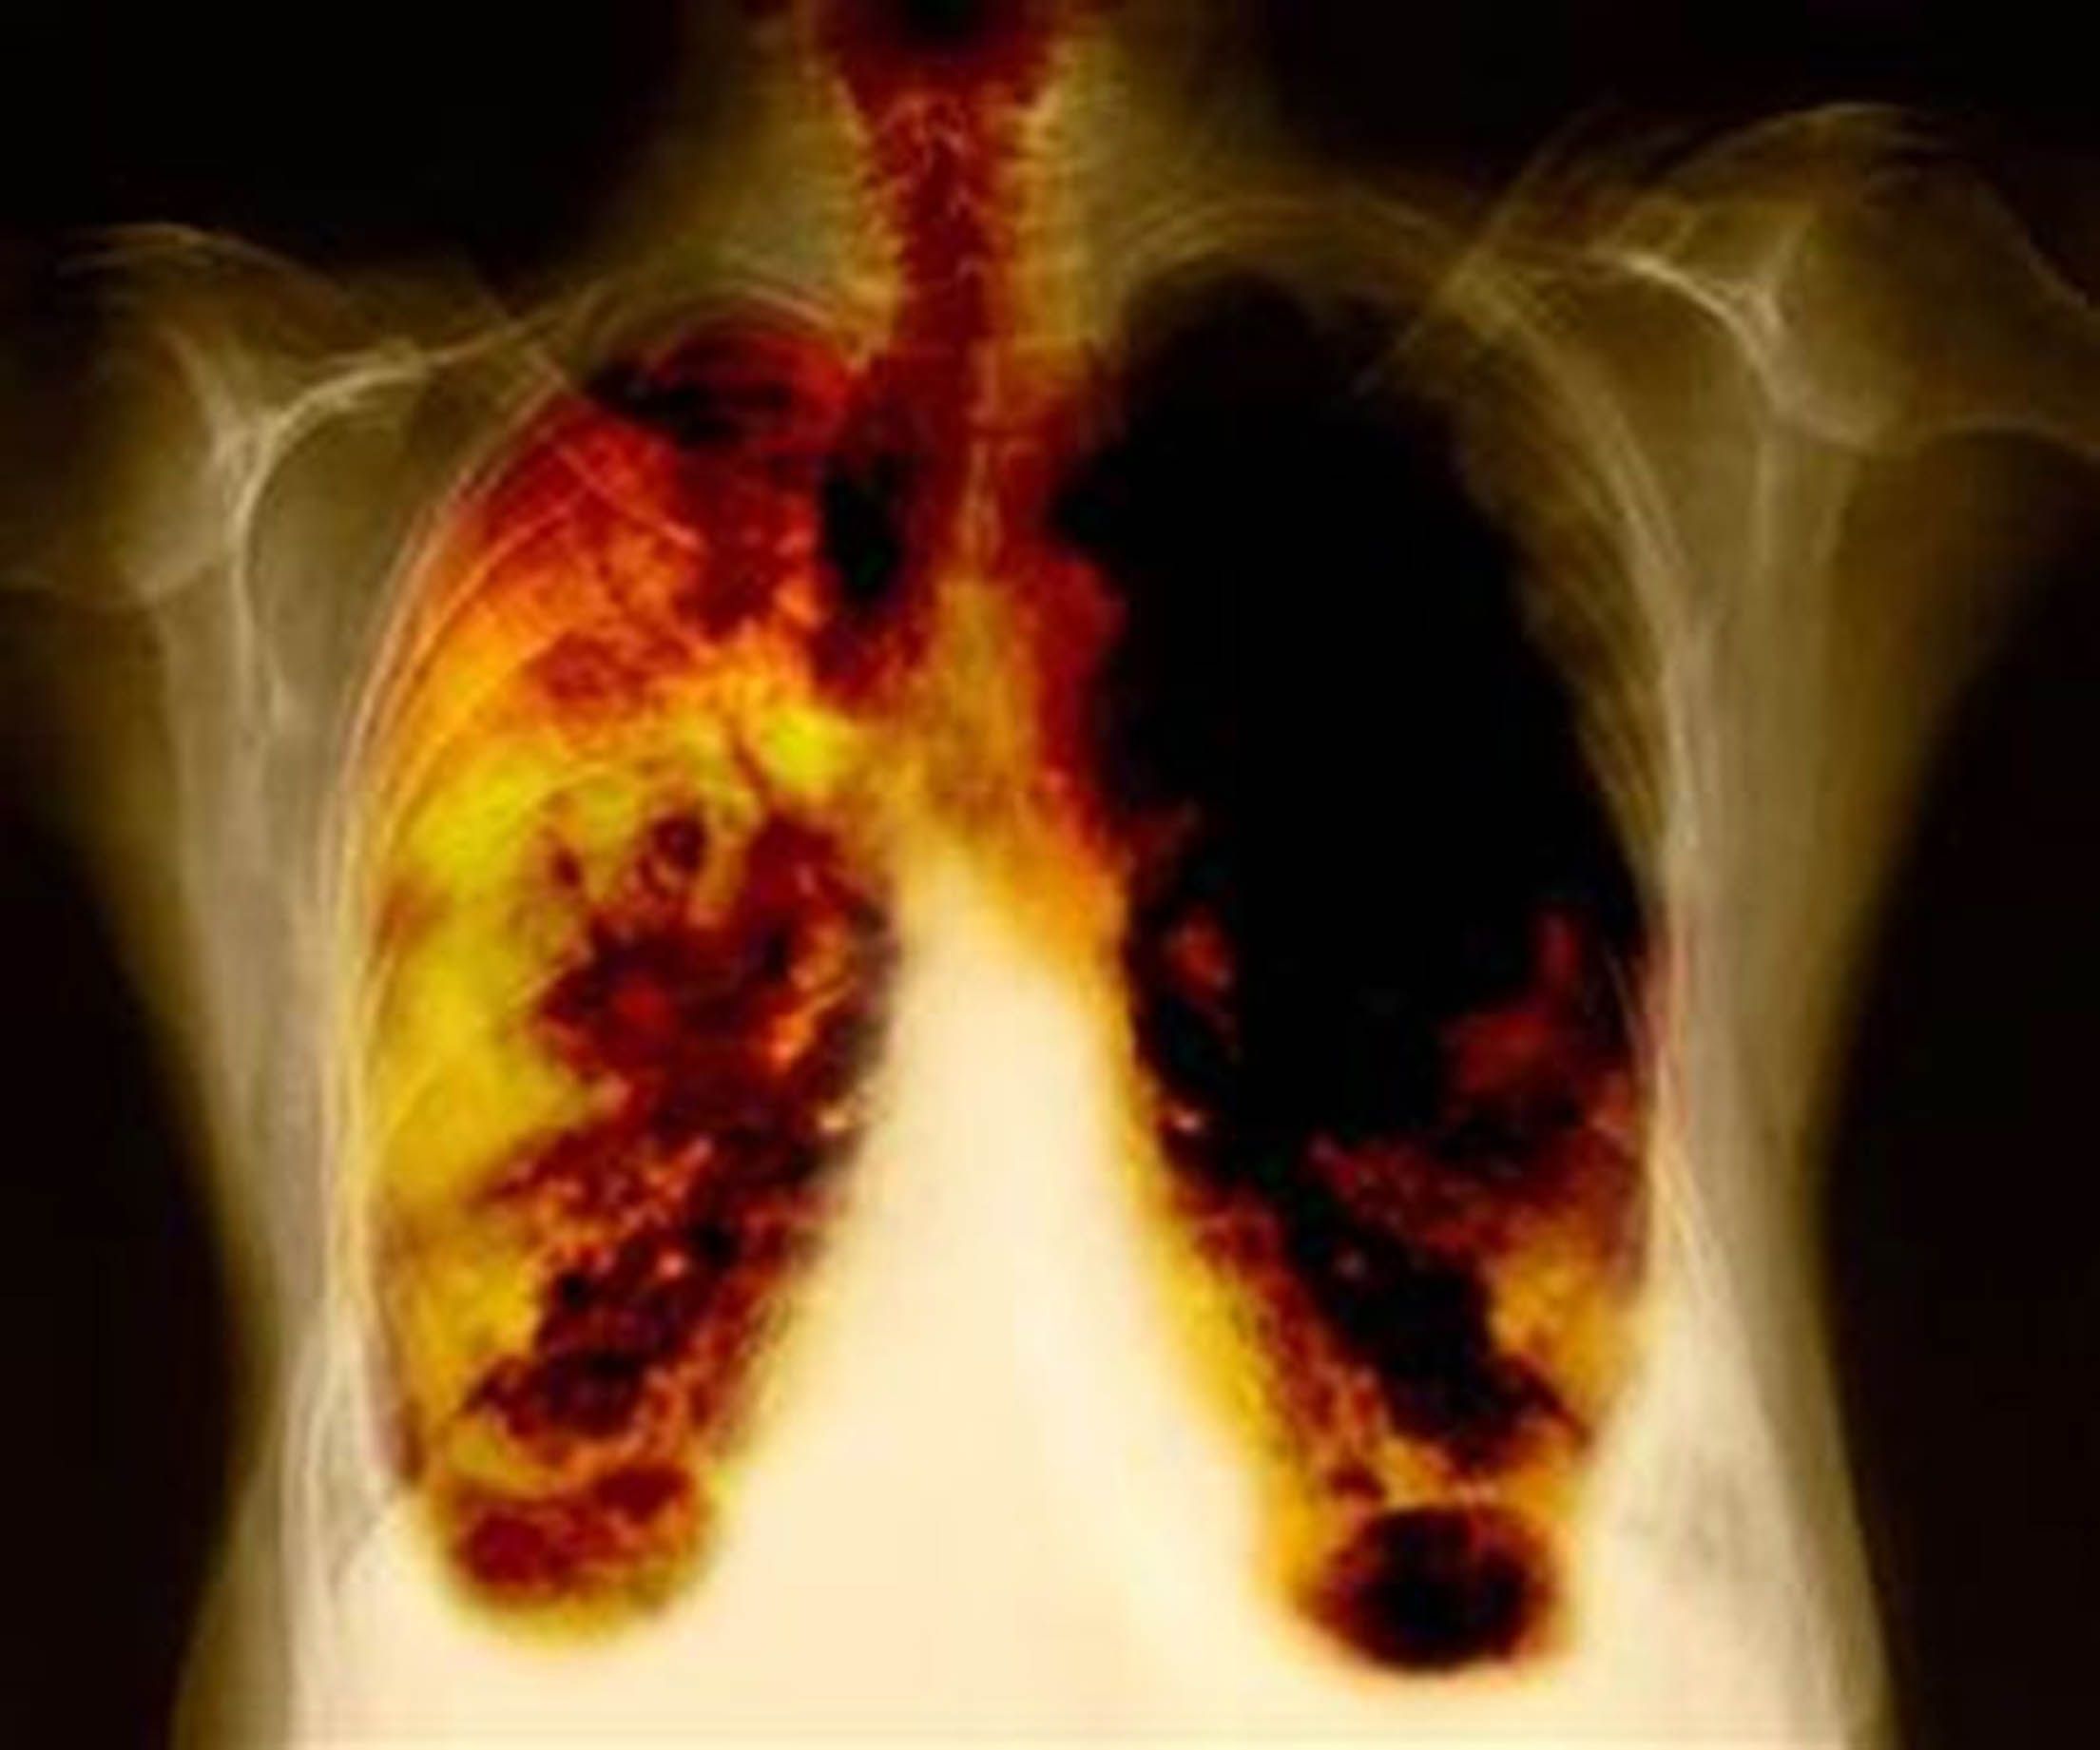

El cáncer de pulmón es un problema mundial de salud causado no sólo por el tabaquismo, sino también por la inhalación de humo de leña y otros contaminantes.